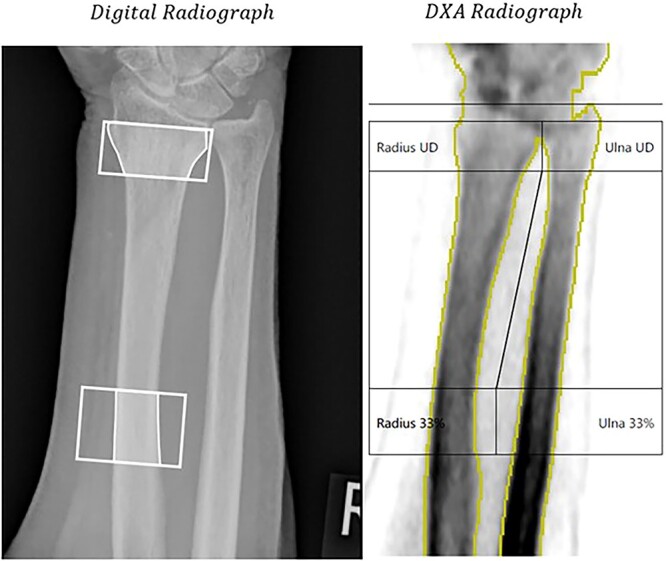

Osteoporosis and associated fractures are an increasingly prevalent concern with an ageing population. This study reports testing of IBEX Bone Health (IBEX BH) software, applied following acquisition of forearm radiographs. IBEX Bone Health analyses the radiograph to measure areal bone mineral density (aBMD) at the examination site. A non-randomized cross-sectional study design was performed involving 261 (254 after exclusions) participants (112/142 m/f; mean age 70.8 years (SD+/-9.0); 53 with osteoporosis). They underwent posterior-anterior distal forearm radiographs; dual X-ray absorptiometry (DXA) of the wrists, hips, and lumbar spine; and questionnaires exploring clinical risk factors. IBEX Bone Health automatically identifies regions of interest (ROI) at the ultra-distal (UD) and distal third (TD) regions of the radius. Analysis investigated area under the receiver operating characteristics curve performance of IBEX BH for prediction of (i) osteoporosis (based on clinical reporting of the hip and spine DXA) and (ii) treatment recommendations by Fracture Risk Assessment Tool (FRAX) inclusive of neck of femur (NoF) areal bone mineral density (aBMD) results following National Osteoporosis Guideline Group (NOGG) guidelines. Area under the receiver operating characteristics curve for osteoporosis prediction at the UD and TD ROIs were 0.86 (99% confidence interval (CI) [0.80, 0.91]) and 0.81 (99% CI [0.75, 0.88]), respectively. Area under the receiver operating characteristics curve for treatment recommendation using FRAX inclusive of NoF aBMD at the UD and TD ROIs were 0.95 (99% CI [0.91, 1.00]) and 0.97 (99% CI [0.93,1.00]), respectively. With a matched sensitivity to FRAX (without NoF aBMD) 0.93 (99% CI [0.78, 0.99]), IBEX BH predicted at the UD and TD ROIs recommended treatment outcomes by NOGG guidelines using FRAX (with NoF aBMD) with specificity 0.89 (99% CI 0.83, 0.94]) and 0.93 (99% CI [0.87, 0.97]), respectively. This is compared with 0.60 (99% CI [0.51, 0.69]) for FRAX (without NoF aBMD). Results demonstrate the potential clinical utility of IBEX BH as an opportunistic screening tool.